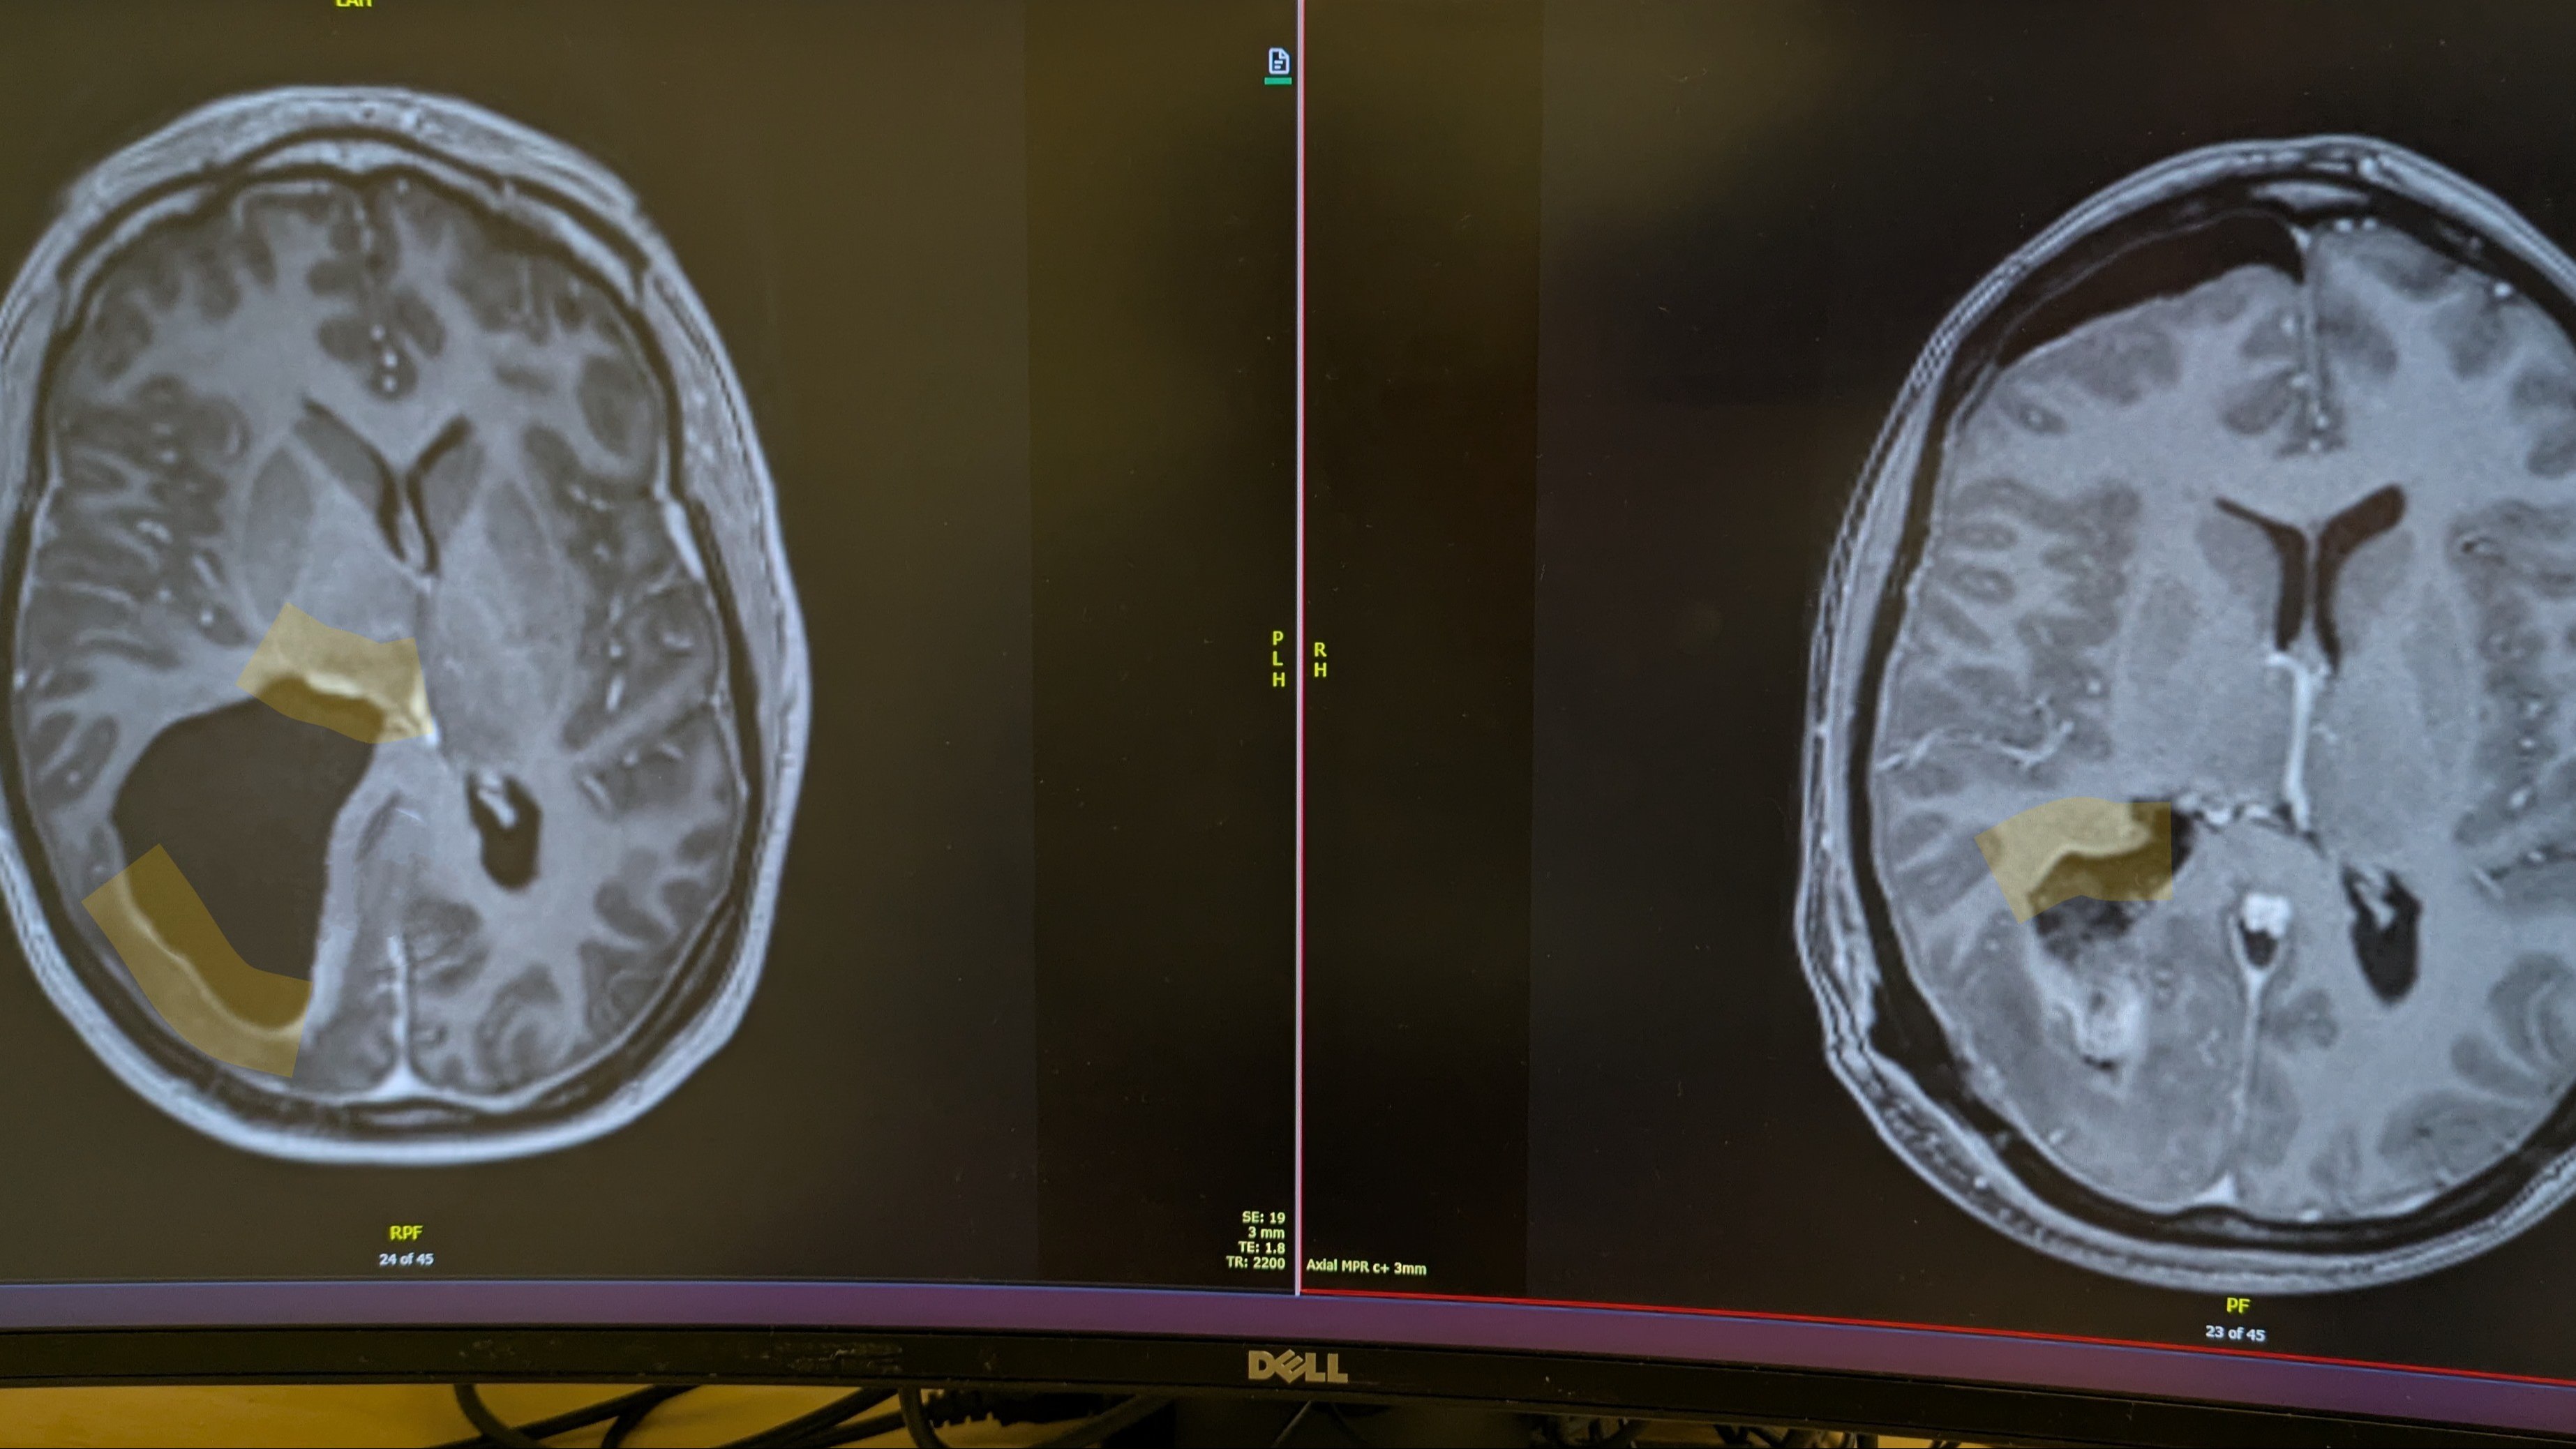

Hi pals, I wanted to share some images of the scans I had before and after brain surgery a few weeks ago. They really show how insanely large the cyst was and what was left after the operation. There is still a fair bit of swelling from radiation and surgery, but the image on the left is with the cyst (it actually got a bit bigger before it came out), with the white sections around the perimeter of the cyst highlighted in yellow being the tumor. The image on the right shows the void where the cyst was. The highlighted section shows what was left of the tumor, which couldn’t be safely removed. The white section which isn’t highlighted is likely a combination of swelling, blood and potentially some more tumor, but it’s still too early to tell for sure. Either way, there’s no cyst, and a hell of a lot less tumor than before. Fun fact - the black section at the top of the right image is an air pocket (this is normal after brain surgery) and I could hear it moving around my head for about a week before it dissipated. Last week I started the second round of chemo to blast what’s left of Brian. This round will last 12 months, with each cycle being 5 days on, 23 days rest, rinse and repeat. The dose will increase for the first 3 months and as long as I can tolerate it, I’ll stay on the highest dose for 9 months. 1 cycle down 11 to go… Following surgery, I’ve had a reduction in headaches, my eyesight has improved and my energy levels are starting to increase. Recovery from surgery has been a mixed bag of emotions, but the scar is looking good and my hair has even started to grow back in fuzzy patches. I still have a long way to go, but I know in my bones that I’m going to win. As always, thank you for your ongoing love and support, it’s one of the main things keeping us going. Love, Em x P.S - I want to say a huge thank you to my beloved dance studio Bottoms Up, for putting on a fundraiser class last weekend, as well as to everyone who has contributed to or shared the fundraiser so far. Please keep sharing it with your networks if you’re able, it has already been an incredible support.